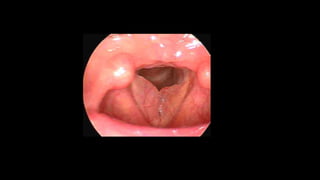

The vocal cords are

apart for breathing

in. The rings of the

trachea (wind pipe)

can be seen. They

are at their widest

apart during a sniff.

The vocal cords blur

once they are vibrating,

but at the instant before

they vibrate, the vocal

cords can be seen in

this shortened position,

slightly bowed.

The arytenoids have

come together

At a high pitch, at

the onset of

phonation, the vocal

cords are stretched.